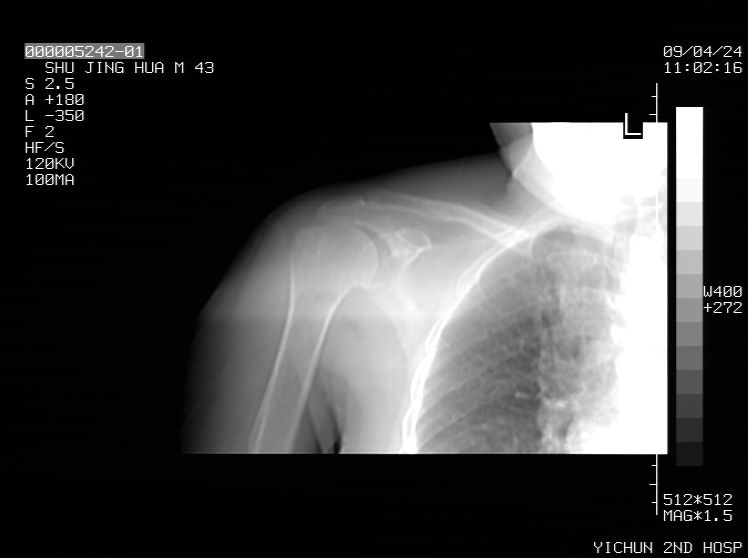

标题: CT19569:请会诊,女50岁,右肩疼痛数月 [打印本页]

标题: CT19569:请会诊,女50岁,右肩疼痛数月

考虑钙化性肩周炎,肱二头肌长腱或相应附属组织钙化

钙化性肌腱炎

是指钙盐沉积在变性肌腱中的一种无菌性炎症,常见于肩关节的肩袖肌腱,引起肩部疼痛和活动受限。分为急性和慢性两种类型,急性型有肩关节突然出现急性疼痛的发作史,夜间可痛醒。